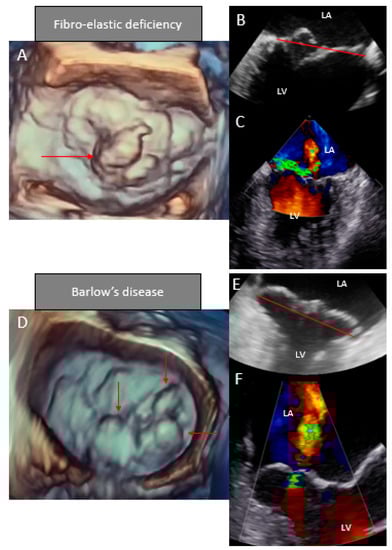

6. Echocardiographic Characteristics

6.2. 3D Echocardiography

| Leaflets | Single segment (usually posterior) prolapse (flail) due to chordal rupture Thickened leaflet tissue (when present) is limited to the level of the prolapsing segment Thin/normal leaflet tissue in non-prolapsing segments | Diffuse excessive valve tissue with multiple segments, bi-leaflet prolapse Thickened leaflets |

| Annulus | Normal of moderate annular dilatation No calcifications | Severe annular dilatation Calcifications could be present Mitral annular disjunction Systolic outward motion during systole (curling) |